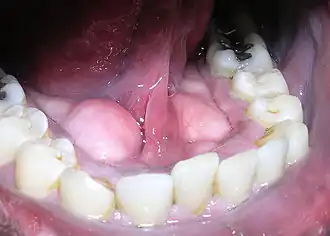

Kamień nazębny (łac. calculus dentalis) – zmineralizowana (zwapniała) płytka nazębna. Powstawanie kamienia nazębnego z płytki nazębnej rozpoczyna się po kilkudziesięciu godzinach od ostatniego czyszczenia zębów[1].

Kamień nazębny składa się głównie z substancji zawartych w ślinie, bakterii próchnicotwórczych i ich produktów przemiany materii, złuszczonych komórek nabłonka, związków wapnia, fosforu i resztek pożywienia.

W zależności od innych substancji dostających się do jamy ustnej, kamień nazębny może przybierać różne odcienie. Zazwyczaj posiada on barwę znacznie ciemniejszą od koloru zębów, która pogłębia się jeszcze przy spożywaniu np. kawy i herbaty lub też wdychaniu dymu papierosowego.